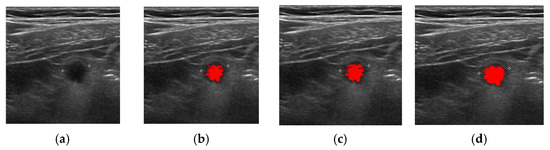

| Method | Successful Images/Total Images |

|---|---|

| FCM | 83/100 |

| ORFCM | 88/100 |

| DFCM | 91/100 |

| DORFCM | 98/100 |

| Accuracy | Precision | Recall | |

|---|---|---|---|

| DORFCM | 84.20% | 83.40% | 85.80% |

| DFCM | 80.80% | 80.90% | 80.20% |

| DORFCM | 84.82% | 83.78% | 86.04% |

| ORFCM | 81.23% | 78.56% | 80.53% |